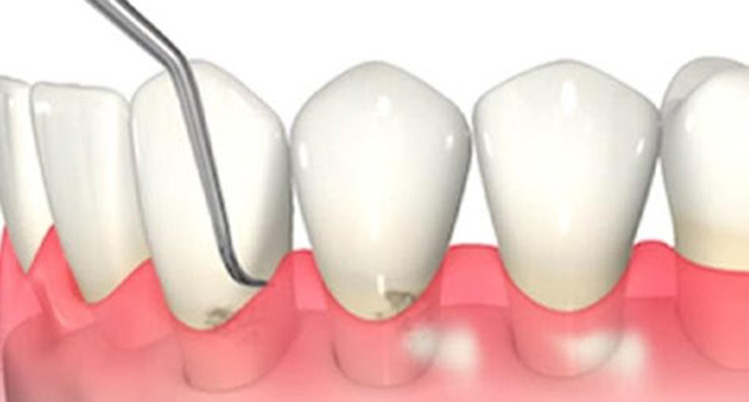

2. スケーリング(歯石除去)

歯科医院で行うクリーニングの中に含まれるもので、専用の機械や器具を使用して歯石を取り除きます。

歯石の表面にはざらつきがあり、プラークが溜まりやすくなるため定期的に除去しましょう。

超音波の振動で汚れを落とすイメージ写真

3. SRP

(スケーリング・ルートプレーニング)

専用の器具を使って、歯ぐきの中にある汚れを除去して、歯の根っこ部分の表面を汚れの付着が起こりにくい状態に仕上げる処置です。

主に、歯ぐきの中にまで歯石が入り込んでいる中等度以上の患者さまに対して行います。痛みが強い場合は、麻酔をして行うこともあります。

歯と歯茎の間の汚れをかき出すイメージイラスト